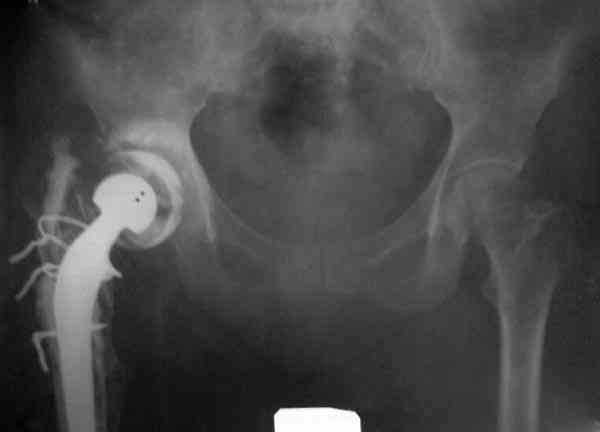

Приглашенный хирург установил ревизионный вариант бедренного компонента без замены ацетабулярного компонента, что осложнилось нагноением и свищами на уровне сустава и средней трети бедра. После двухгодичного безуспешного лечения перевязками и антибиотиками больная обратилась к нам на консультацию.

№3-6 снимки с осложнением

и последние снимки.